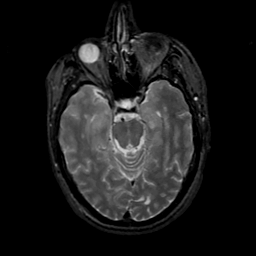

MR Study #18, July 21, 1991 -- Slice #18